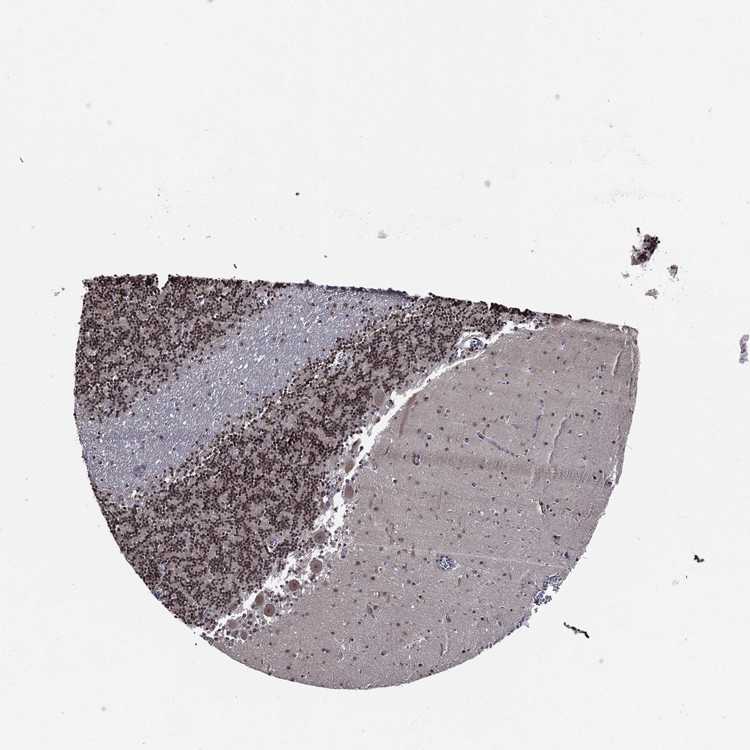

CEREBELLUM - Antibody stainingi

Antibody staining in the annotated cell types in the current human tissue is reported as not detected, low, medium, or high, based on conventional immunohistochemistry profiling in selected tissues. This score is based on the combination of the staining intensity and fraction of stained cells.

Each image is clickable and will lead to virtual microscopy that enables deeper exploration of all samples and also displays staining intensity scores, fraction scores and subcellular localization as well as patient and tissue information for each sample.

Antibody HPA043206

Purkinje cells Low

Cells in granular layer High

Cells in molecular layer Low